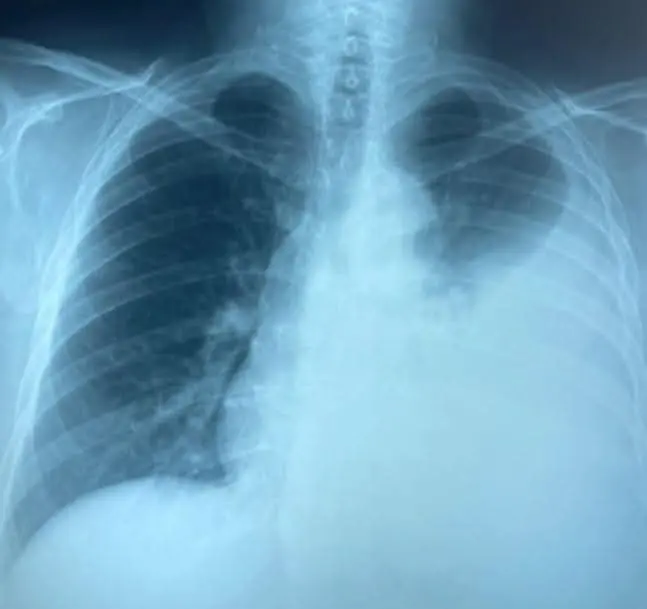

Frente Frío 14: Especialistas advierten aumento de enfermedades pulmonares por frente frío

Ante los frentes fríos, las personas con malestares pulmonares deben cuidarse mucho más, al igual que personas mayores y menores de edad.

Con la llegada de los frentes fríos el incremento de enfermedades pulmonares es también producto de no ventilar las áreas donde pueden haber personas enfermas, sin utilizar cubrebocas.

Si las personas padecieron COVID en la pandemia, una de sus secuelas es la fibrosis pulmonar, pequeñas cicatrices que impiden el correcto funcionamiento de estos órganos vitales.